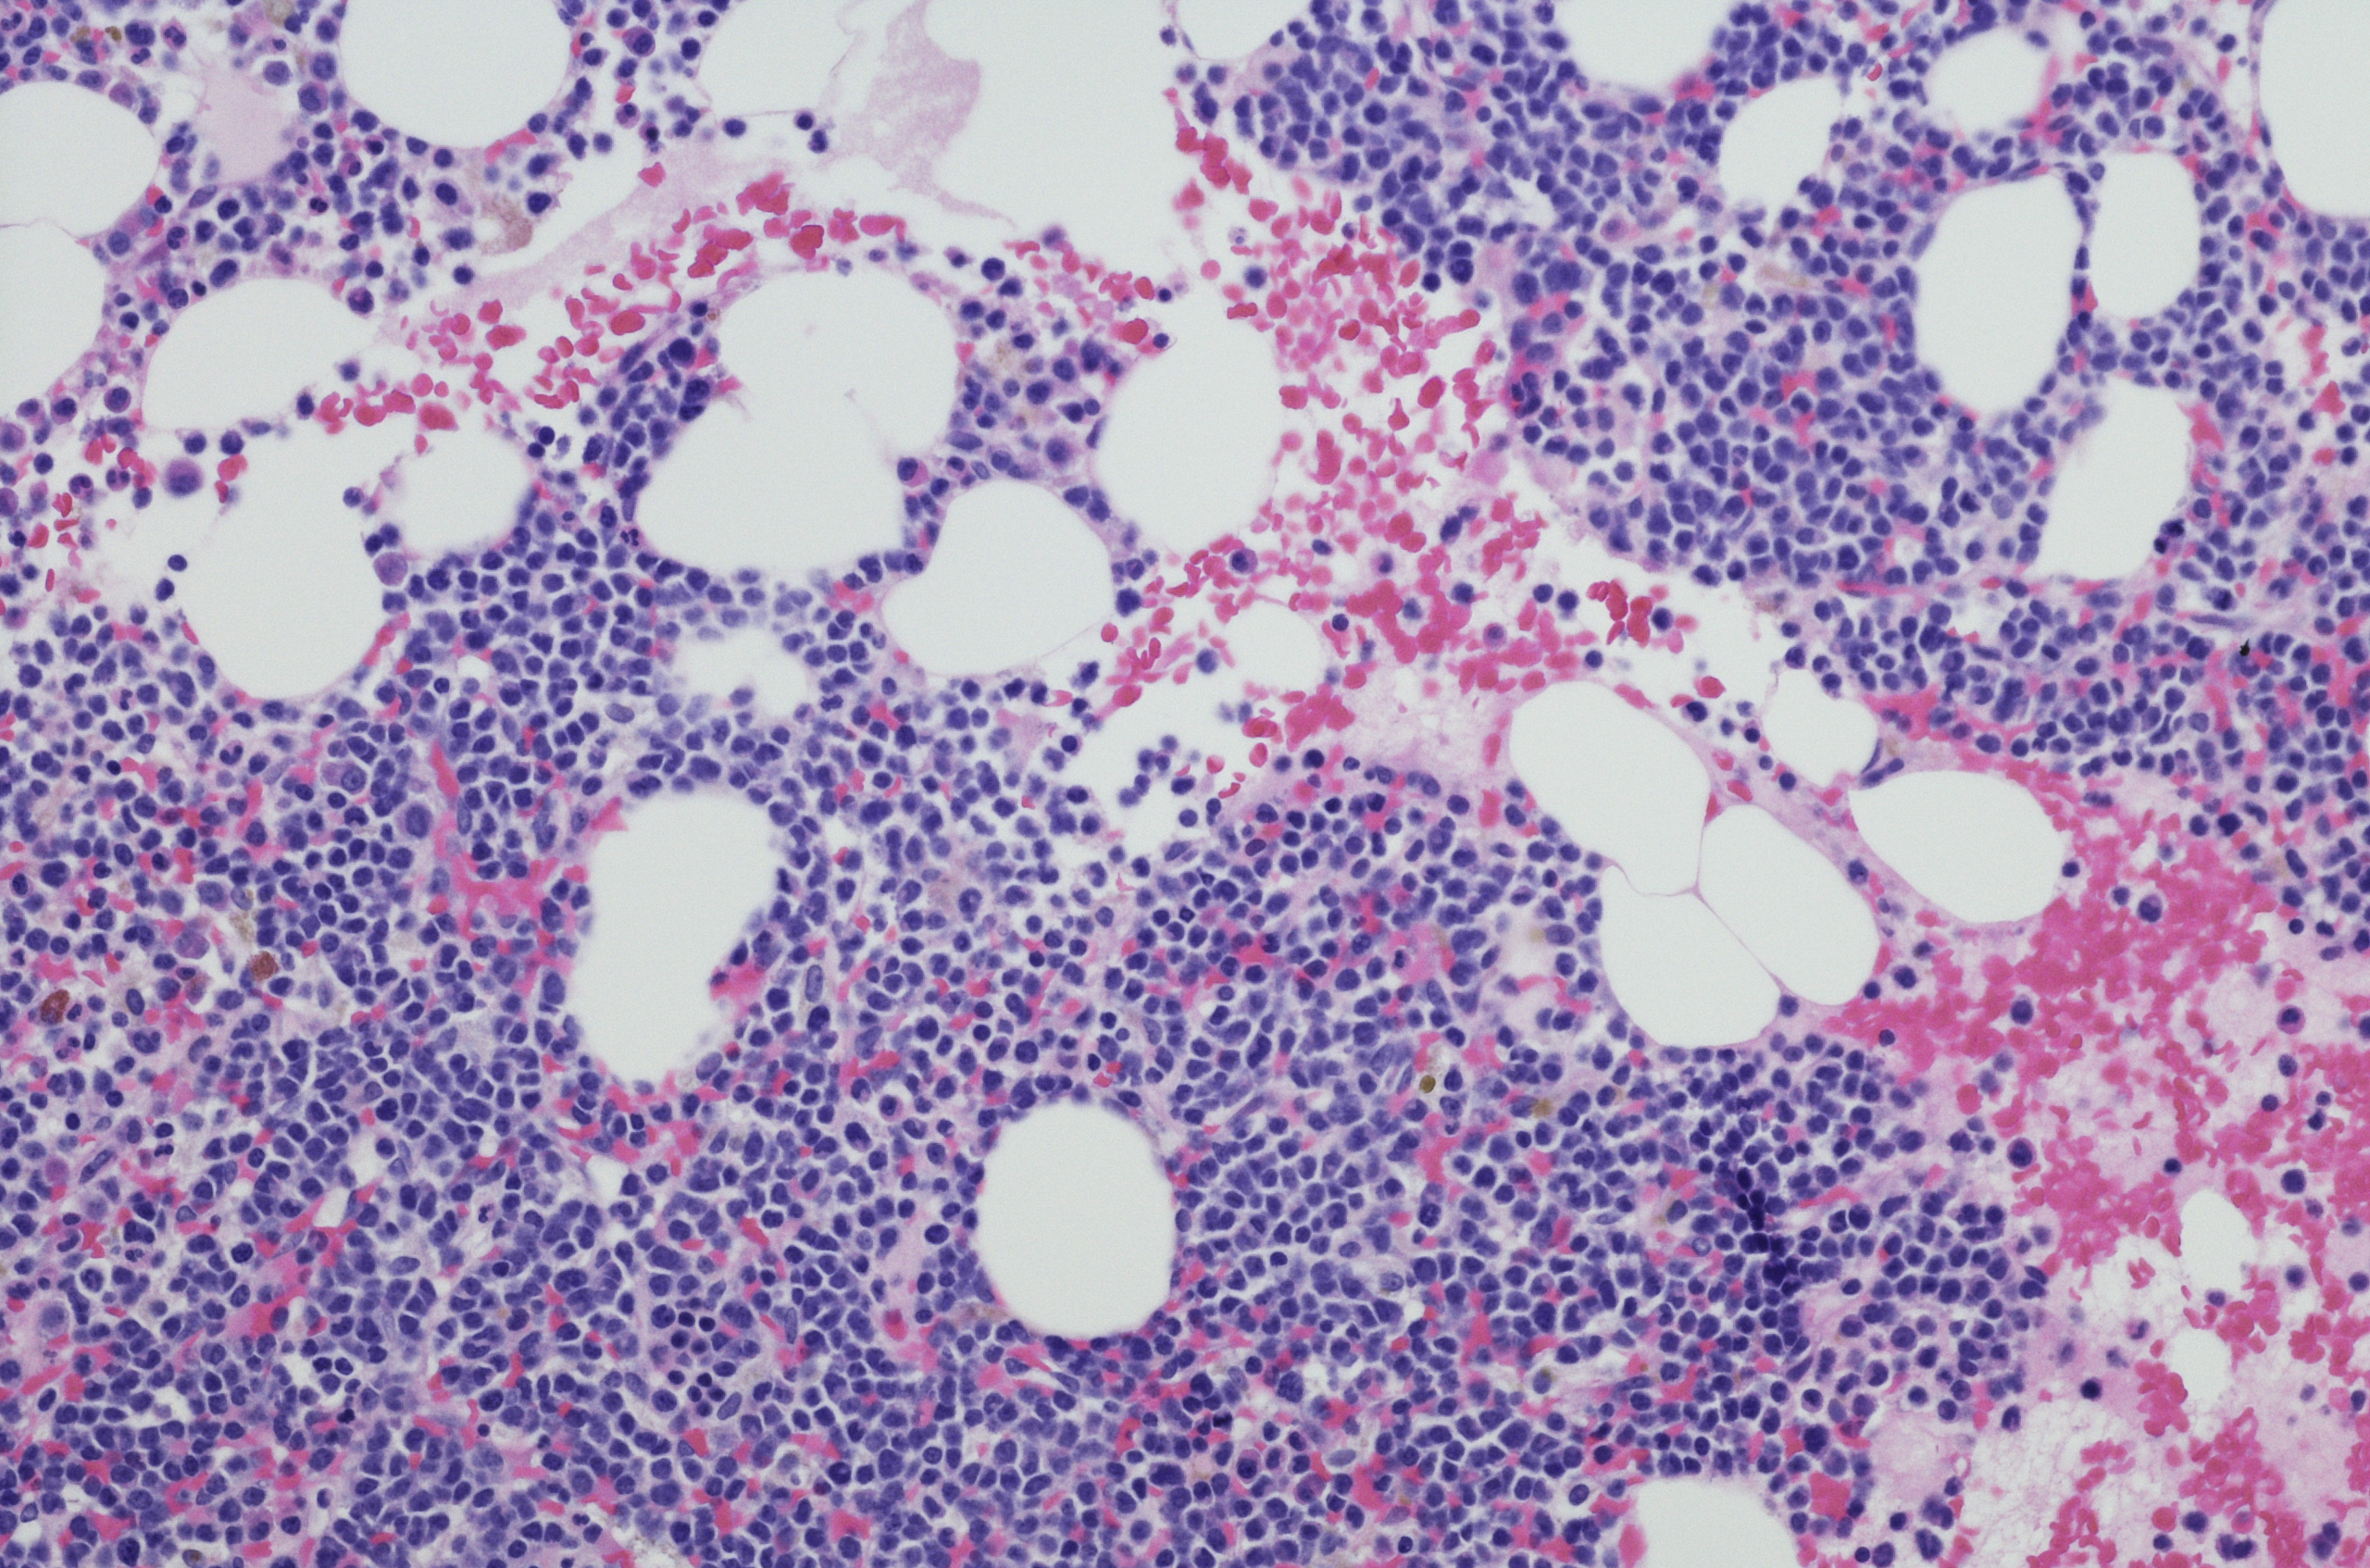

Myeloma arises in our plasma cells, which are mature white blood cells and form part of our immune system. When the myeloma cells start to abnormally reproduce, they form tumours that accumulate in the bone marrow or on the surface of different bones throughout the body. These tumours secrete chemicals that stimulate other bone marrow cells to remove calcium from the bone – resulting in weaker, more brittle bones.

Another detection method is a bone marrow biopsy which is used to examine the cells from the marrow.

While myeloma is typically detected through blood and urine tests, x-rays or scans of the bones might also be performed to determine if there are any weaknesses in the bone, or erosion from the myeloma cells. A bone marrow biopsy (which will take a small sample of bone marrow for examination) is also often required.